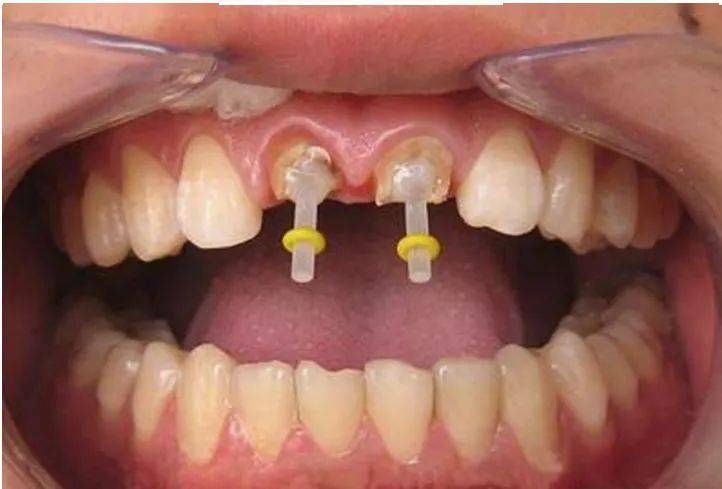

一些人在进行根管治疗后,会进行牙齿打桩。牙齿打桩是指在患者牙齿缺损较大,或因为外伤等原因只剩下牙根时,因剩下的牙齿过短或力量过于薄弱,不能用修复体直接修复,需要给牙根里打桩,加固并延长折断的牙齿,以使假牙能获得足够的力量固定。

牙齿打桩是指插入根管内的部分,利用摩擦力和粘固力、粘接力获得固位,进而为最终修复体提供固位。

牙齿打桩的材料有哪些?

牙齿打桩的材料有纤维桩和金属桩两大类。其中金属桩的材料又分为不锈钢、金钯合金、金铂合金等。如果是前牙,建议使用纤维桩,因为它耐腐蚀性强、不含金属不影响医学检查,不容易引起根折,美观性能好,可以配合全瓷牙适用。而如果是后牙,使用金属桩比较合适,因为处在后牙,对美观的要求性不需要很高,金属桩不易导致牙根折裂,耐腐蚀。